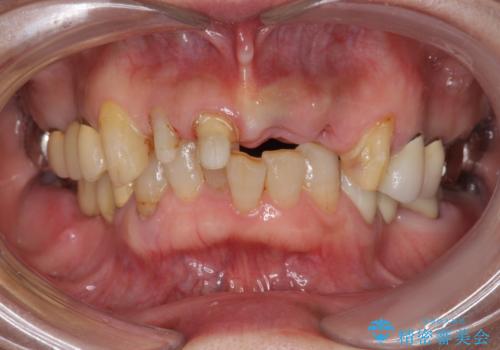

- 歩行中に躓いて転倒し、前歯2本がグラグラになってしまい痛み・審美性の改善を求めて来院されました。

X線検査・視診より強くぶつけた前歯は折れてしまい、抜歯が必要な状況です。

元々の噛み合わせが深く(ディープバイト)、転んで顎を強打したことで上顎前歯2本が根元から折れてしまい抜歯をしなければいけない状況となってしまいました。